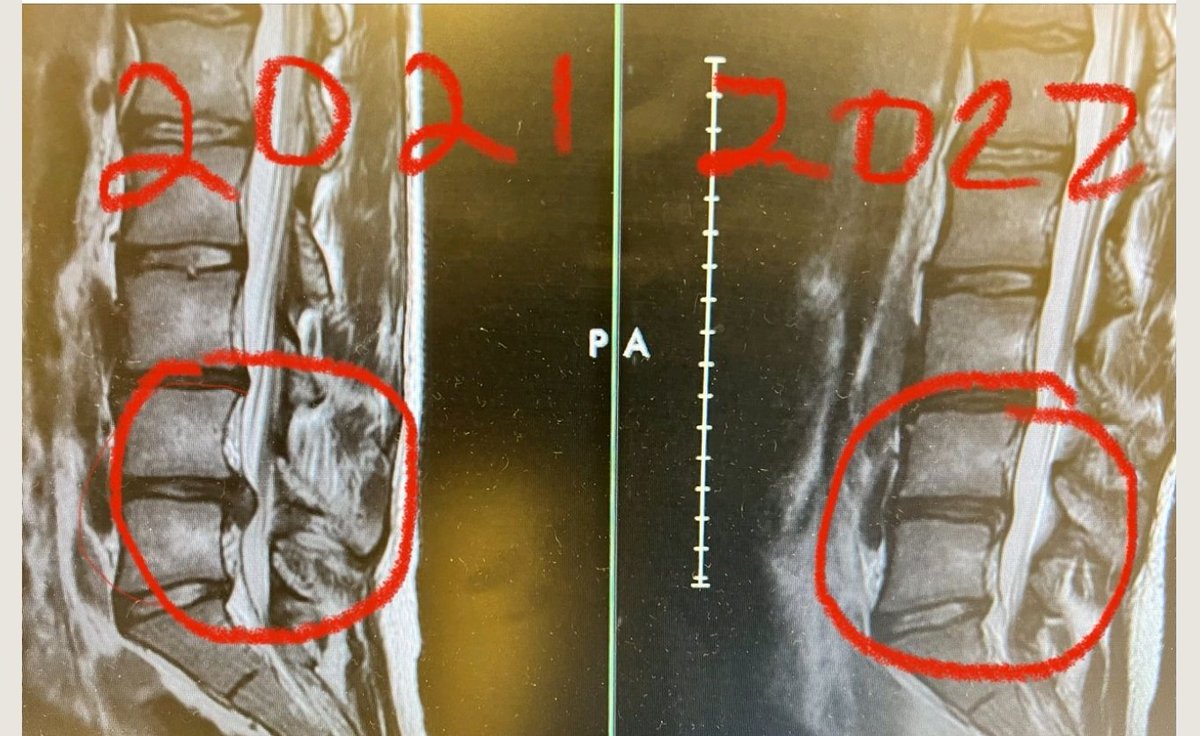

٢-انتفاخ المادة اللينة داخل الأقراص وتضغط على احد الاعصاب أو تمزُّق هذه الاقراص، وغالباً ما يظهر ذلك في

الاشعة السينية او صور الرنين المغناطيسي.